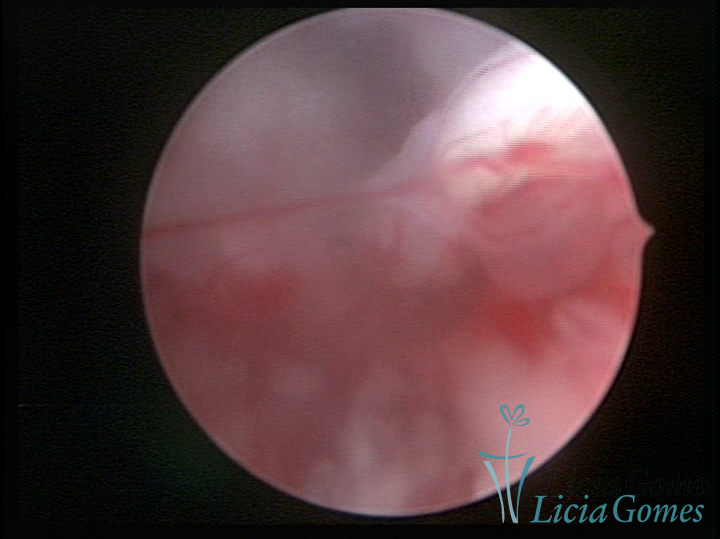

A histeroscopia permite analisar as características da superfície endometrial, não podendo avaliar a profundidade ou o grau de invasão miometrial.

Mas poderá verificar se as lesões são do tipo: focal; regional ou difusa